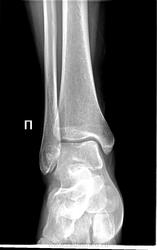

Вот и возникает вопрос - чем же в этом месте так вдавило кортекс (не сломав мыщелков). Насчет кортикального осколка по переднему контуру ББК - может быть.

Дискуссия была знатная. Но в мои цели это не входит. Изначально непонятен механизм межмыщелковой импрессии без перелома мыщелков. Может, травматологи в курсе? Первый снимок непосредственно на 3 или 4 день после травмы.

Как вариант... А если в обратную сторону, тоже может быть?

Вряд-ли. Передний край пилона не выступает книзу, да и жесткого упора в блок передним краем ББК при разгибании стопы не произойдет, даже если предположить столкновение стопы с опорой подушками плюсны.